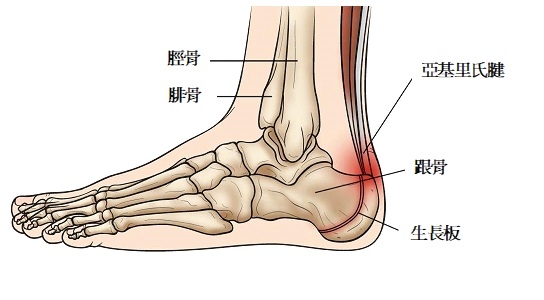

撰文:林偉雄物理治療師 (Mr. Warren Lam, Registered Physiotherapist)11歲的明仔自細便喜歡運動,不論是跑步、足球、籃球及羽毛球等都會參與。不過最近一星期開始,每做完運動便感到右腳跟疼痛,行路甚至會一柺一柺。媽媽擔心明仔是否扭傷,便帶他來求醫,經檢查後,診斷他是患上「跟骨骨骺炎」。跟骨骨骺炎(Sever’s Disease)是指位於跟骨後方的生長板(Growth Plate)發炎而引致的症狀,多發生於8-14的青少年身上。他們的跟骨末端都會有一塊生長板「骨骺」覆蓋著。當跟骨生長板仍未閉合,而小朋友經常參與各類需要跑、跳的運動例如是跑步、足球、籃球或跳舞等),便會因為小腿肌腱反覆拉扯生長板,而出現重複性的損傷引致發炎及痛楚。跟骨骨骺炎一般不會有外傷史,亦不會有明顯的紅、腫及變形。常見的症狀包括:

青少年足跟痛有機會是患上「跟骨骨骺炎」 (Sever’s Disease) 發育中的青少年,足跟的生長板仍未閉合,容易因為過度運動而引致重覆性損傷及發炎

X光下所見的跟骨生長板 小腿伸展運動